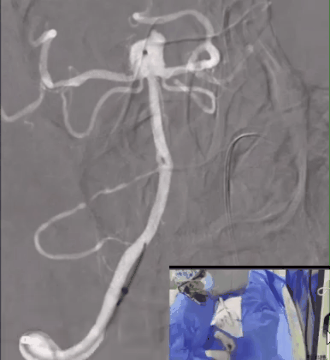

WEB™解脱:解脱前进行造影评估,通过造影结果发现WEB™充分贴壁,瘤颈密封良好。

透视下,将VIA回撤至距离近端WEB™显影标记点3~4mm位置,对装置进行解脱。

解脱后再次造影,多角度提示动脉瘤瘤腔内有明显造影剂滞留,基底动脉及其分支通畅。